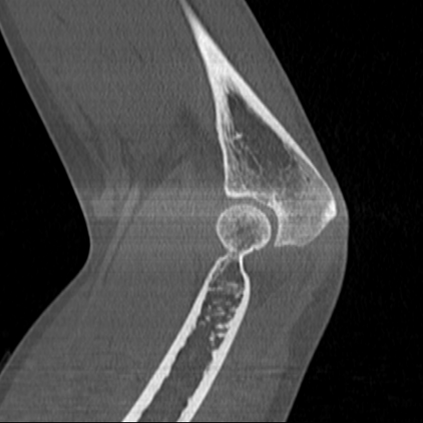

CT reconstruction provides radiologists with images for diagnosis and treatment, yet current deep learning methods are typically limited to specific anatomies and datasets, hindering generalization ability to unseen anatomies and lesions. To address this, we introduce the Multi-Organ medical image REconstruction (MORE) dataset, comprising CT scans across 9 diverse anatomies with 15 lesion types. This dataset serves two key purposes: (1) enabling robust training of deep learning models on extensive, heterogeneous data, and (2) facilitating rigorous evaluation of model generalization for CT reconstruction. We further establish a strong baseline solution that outperforms prior approaches under these challenging conditions. Our results demonstrate that: (1) a comprehensive dataset helps improve the generalization capability of models, and (2) optimization-based methods offer enhanced robustness for unseen anatomies. The MORE dataset is freely accessible under CC-BY-NC 4.0 at our project page https://more-med.github.io/